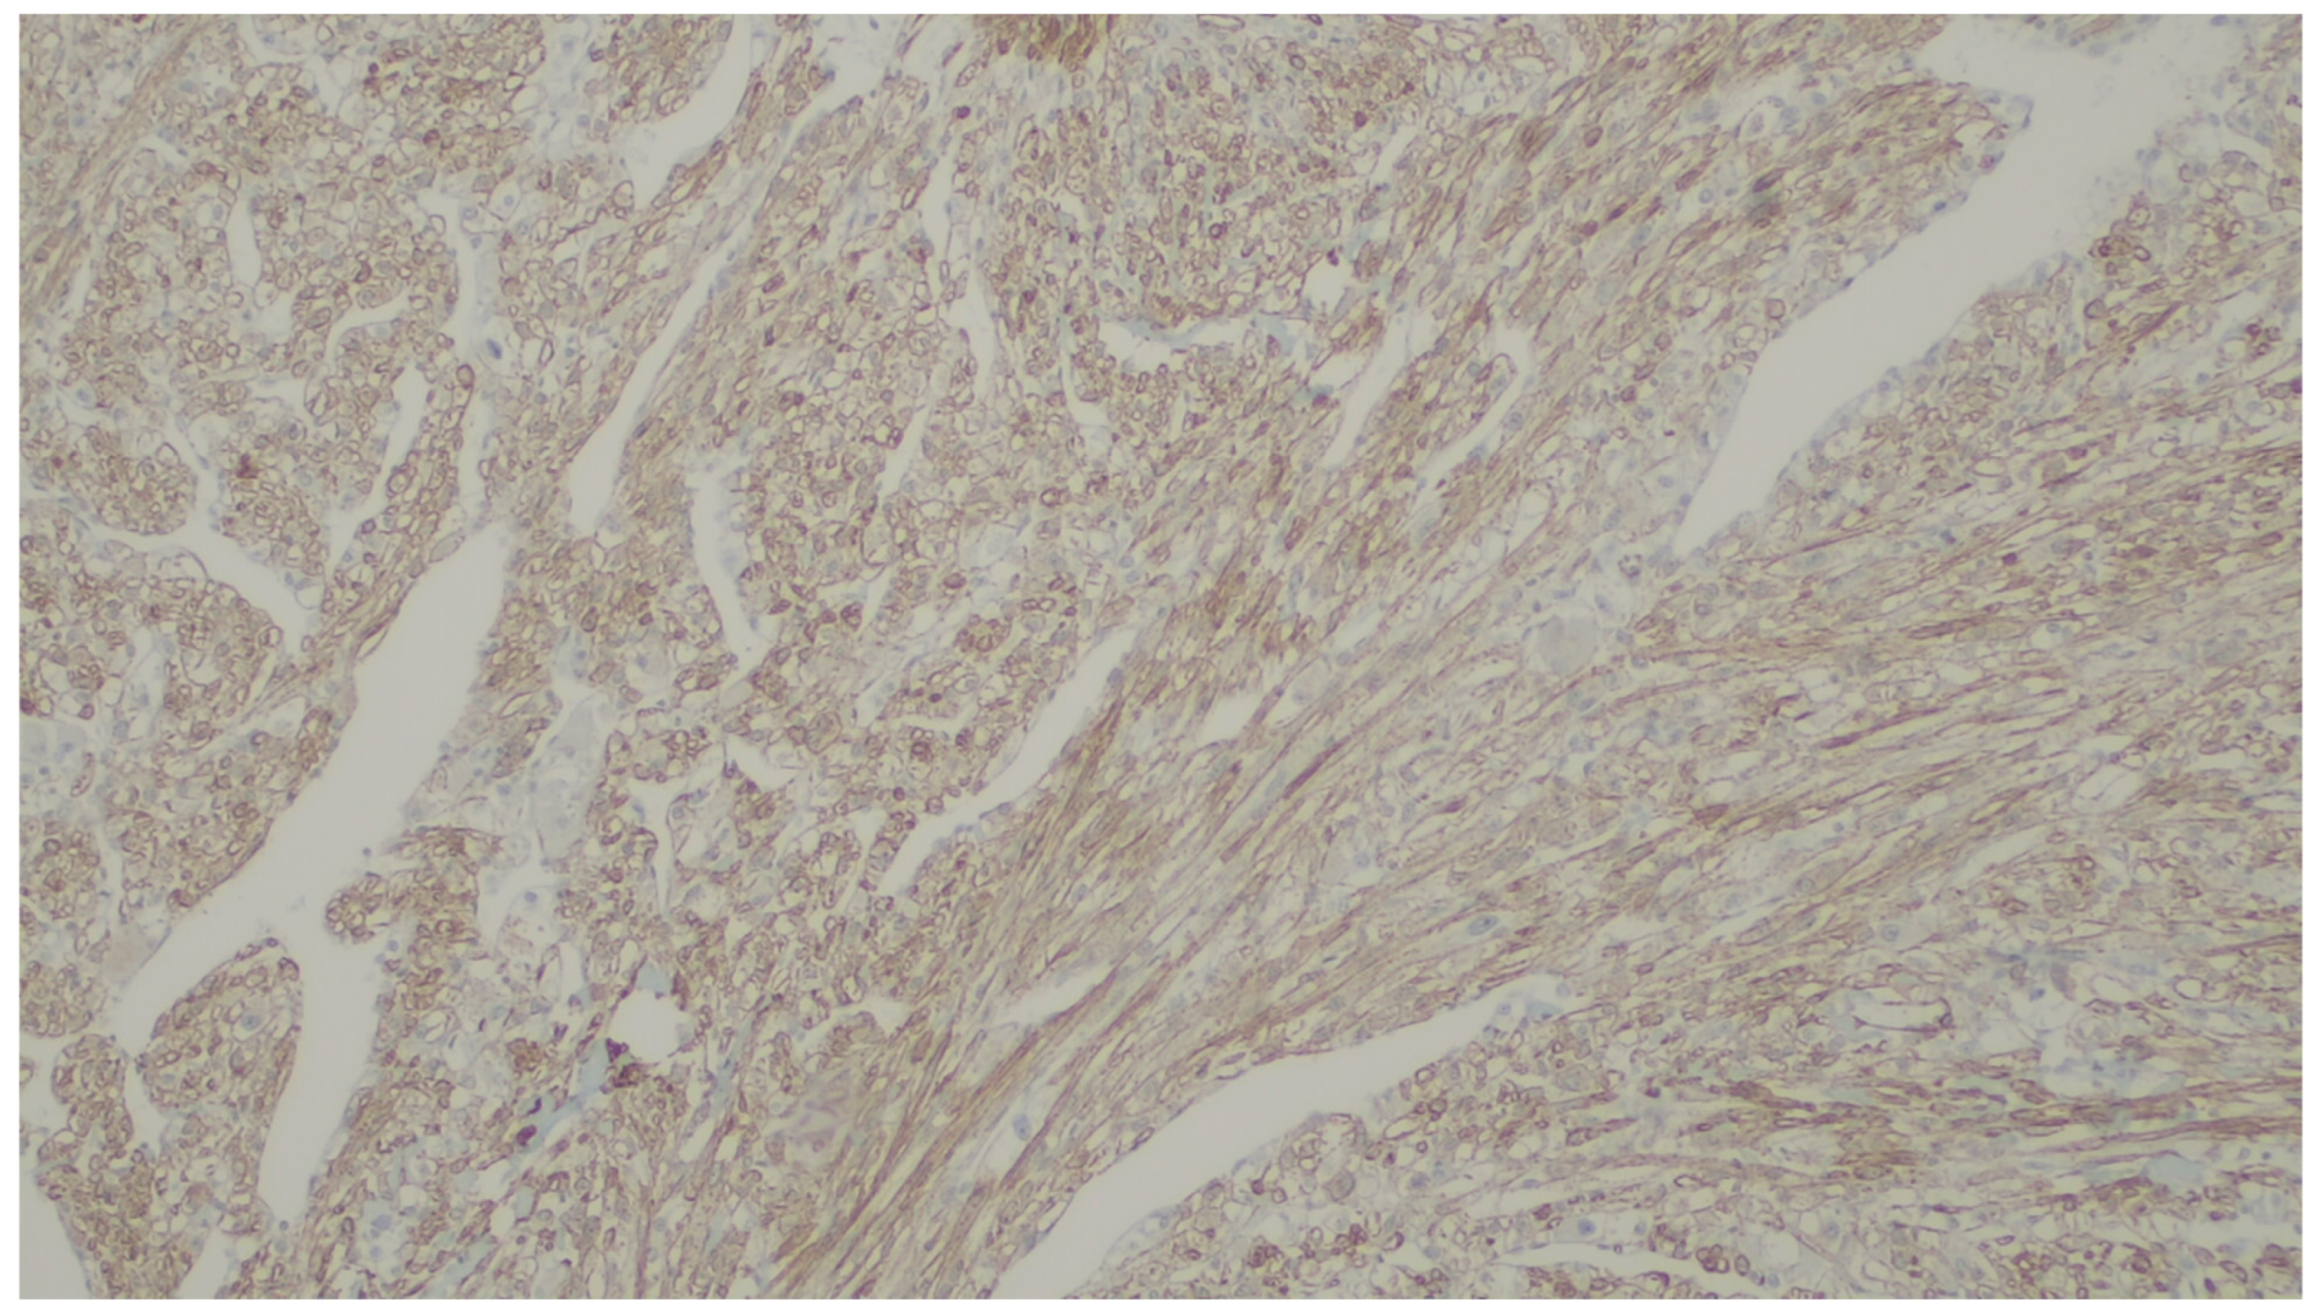

| PEComa | Rare | Colon and small intestine | Symptoms are not specific | Nested, trabecular, and alveolar architecture, surrounded by a delicate vasculature; the cells are usually epithelioid with round to oval nuclei with a granular eosinophilic cytoplasm, but a minority of spindle cells can be seen | α-SMA, desmin, HMB-45 Melan-A, MiTF |